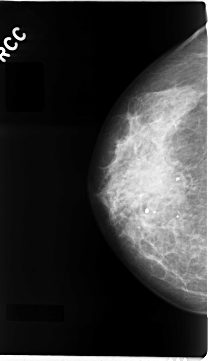

C_0065_1.RIGHT_CC

RIGHT_CC LINES 4688 PIXELS_PER_LINE 2704 BITS_PER_PIXEL 12 RESOLUTION 50 NON_OVERLAY